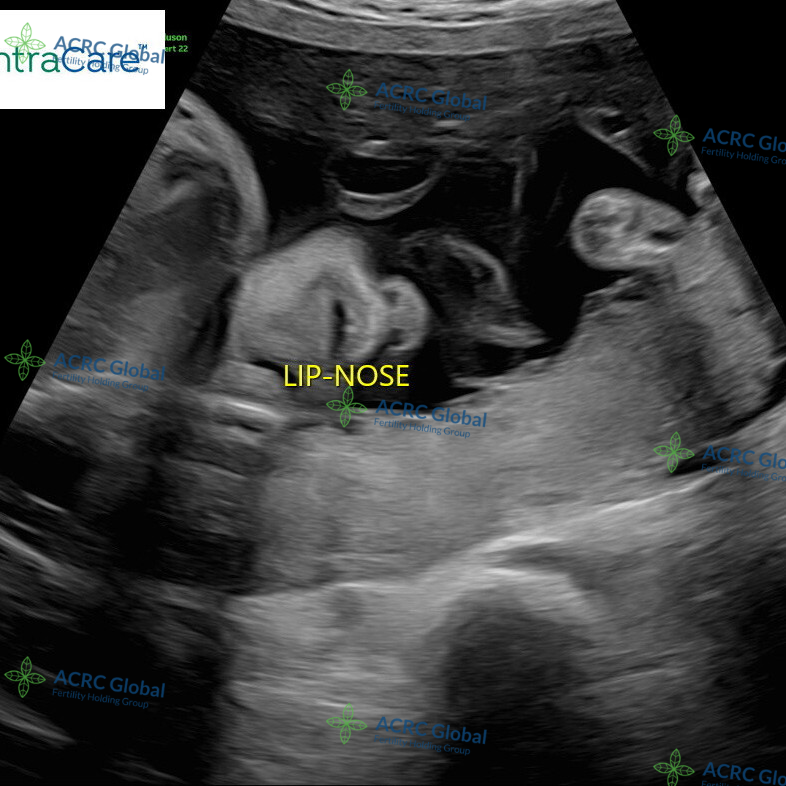

28周宝宝B超孕检

爱妈J已经进入孕28周,最近的B超检查显示,宝宝的发育一切良好。五官和四肢已经清晰可见,脸蛋的轮廓愈发可爱,甚至小脑袋上已经长出了柔软的头发。宝宝的手指和脚趾也在逐渐形成,整个模样越来越清晰,仿佛正在和外界悄悄打招呼。准父母看到这些健康的发育情况,心里感到无比踏实,他们已经迫不及待地期待与宝宝见面的那一天。

五官四肢清晰可见